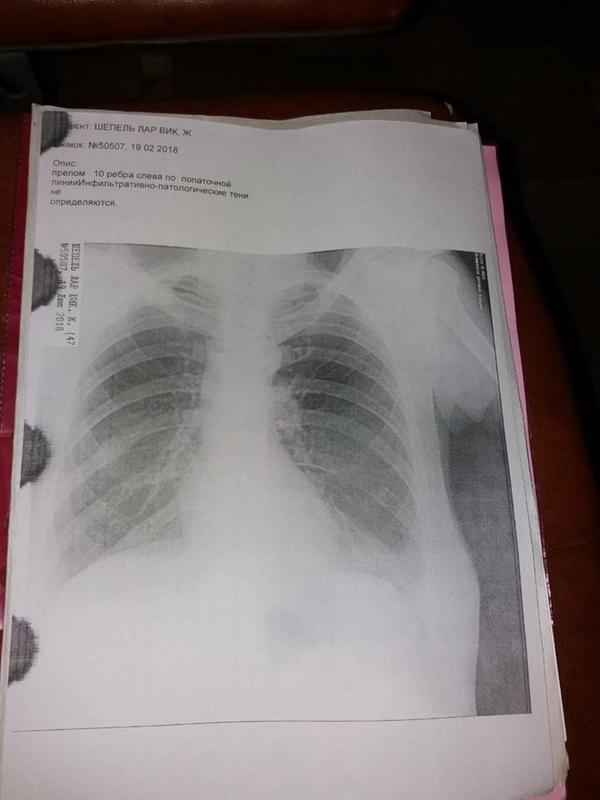

Теперь женщина находится в хирургическом отделении с диагнозом "легкий приступ панкреатита", а лечат ей рваную рану на ноге и перелом 10 ребра.